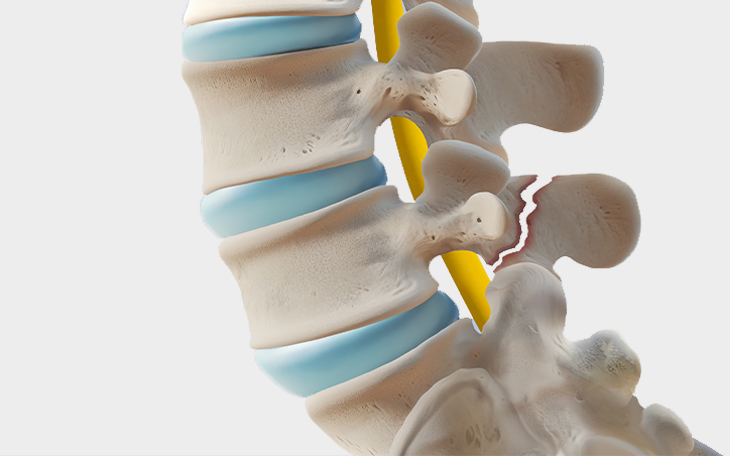

Ein Bandscheibenvorfall entsteht, wenn das weiche Innere einer Bandscheibe (Gallertkern) durch einen Riss im äußeren Faserring (Anulus fibrosus) austritt und auf umliegende Nerven oder das Rückenmark drückt.

Ein Bandscheibenvorfall tritt auf, wenn der innere, gelartige Kern der Bandscheibe (Nucleus pulposus) durch den äußeren Ring (Anulus fibrosus) hindurchtritt und auf benachbarte Nerven oder Rückenmark drückt. Bei einer Bandscheibenprotrusion wölbt sich der innere Kern (Nucleus pulposus) der Bandscheibe aus, bleibt jedoch innerhalb des äußeren Faserrings (Anulus fibrosus). Der Faserring ist dabei noch intakt.